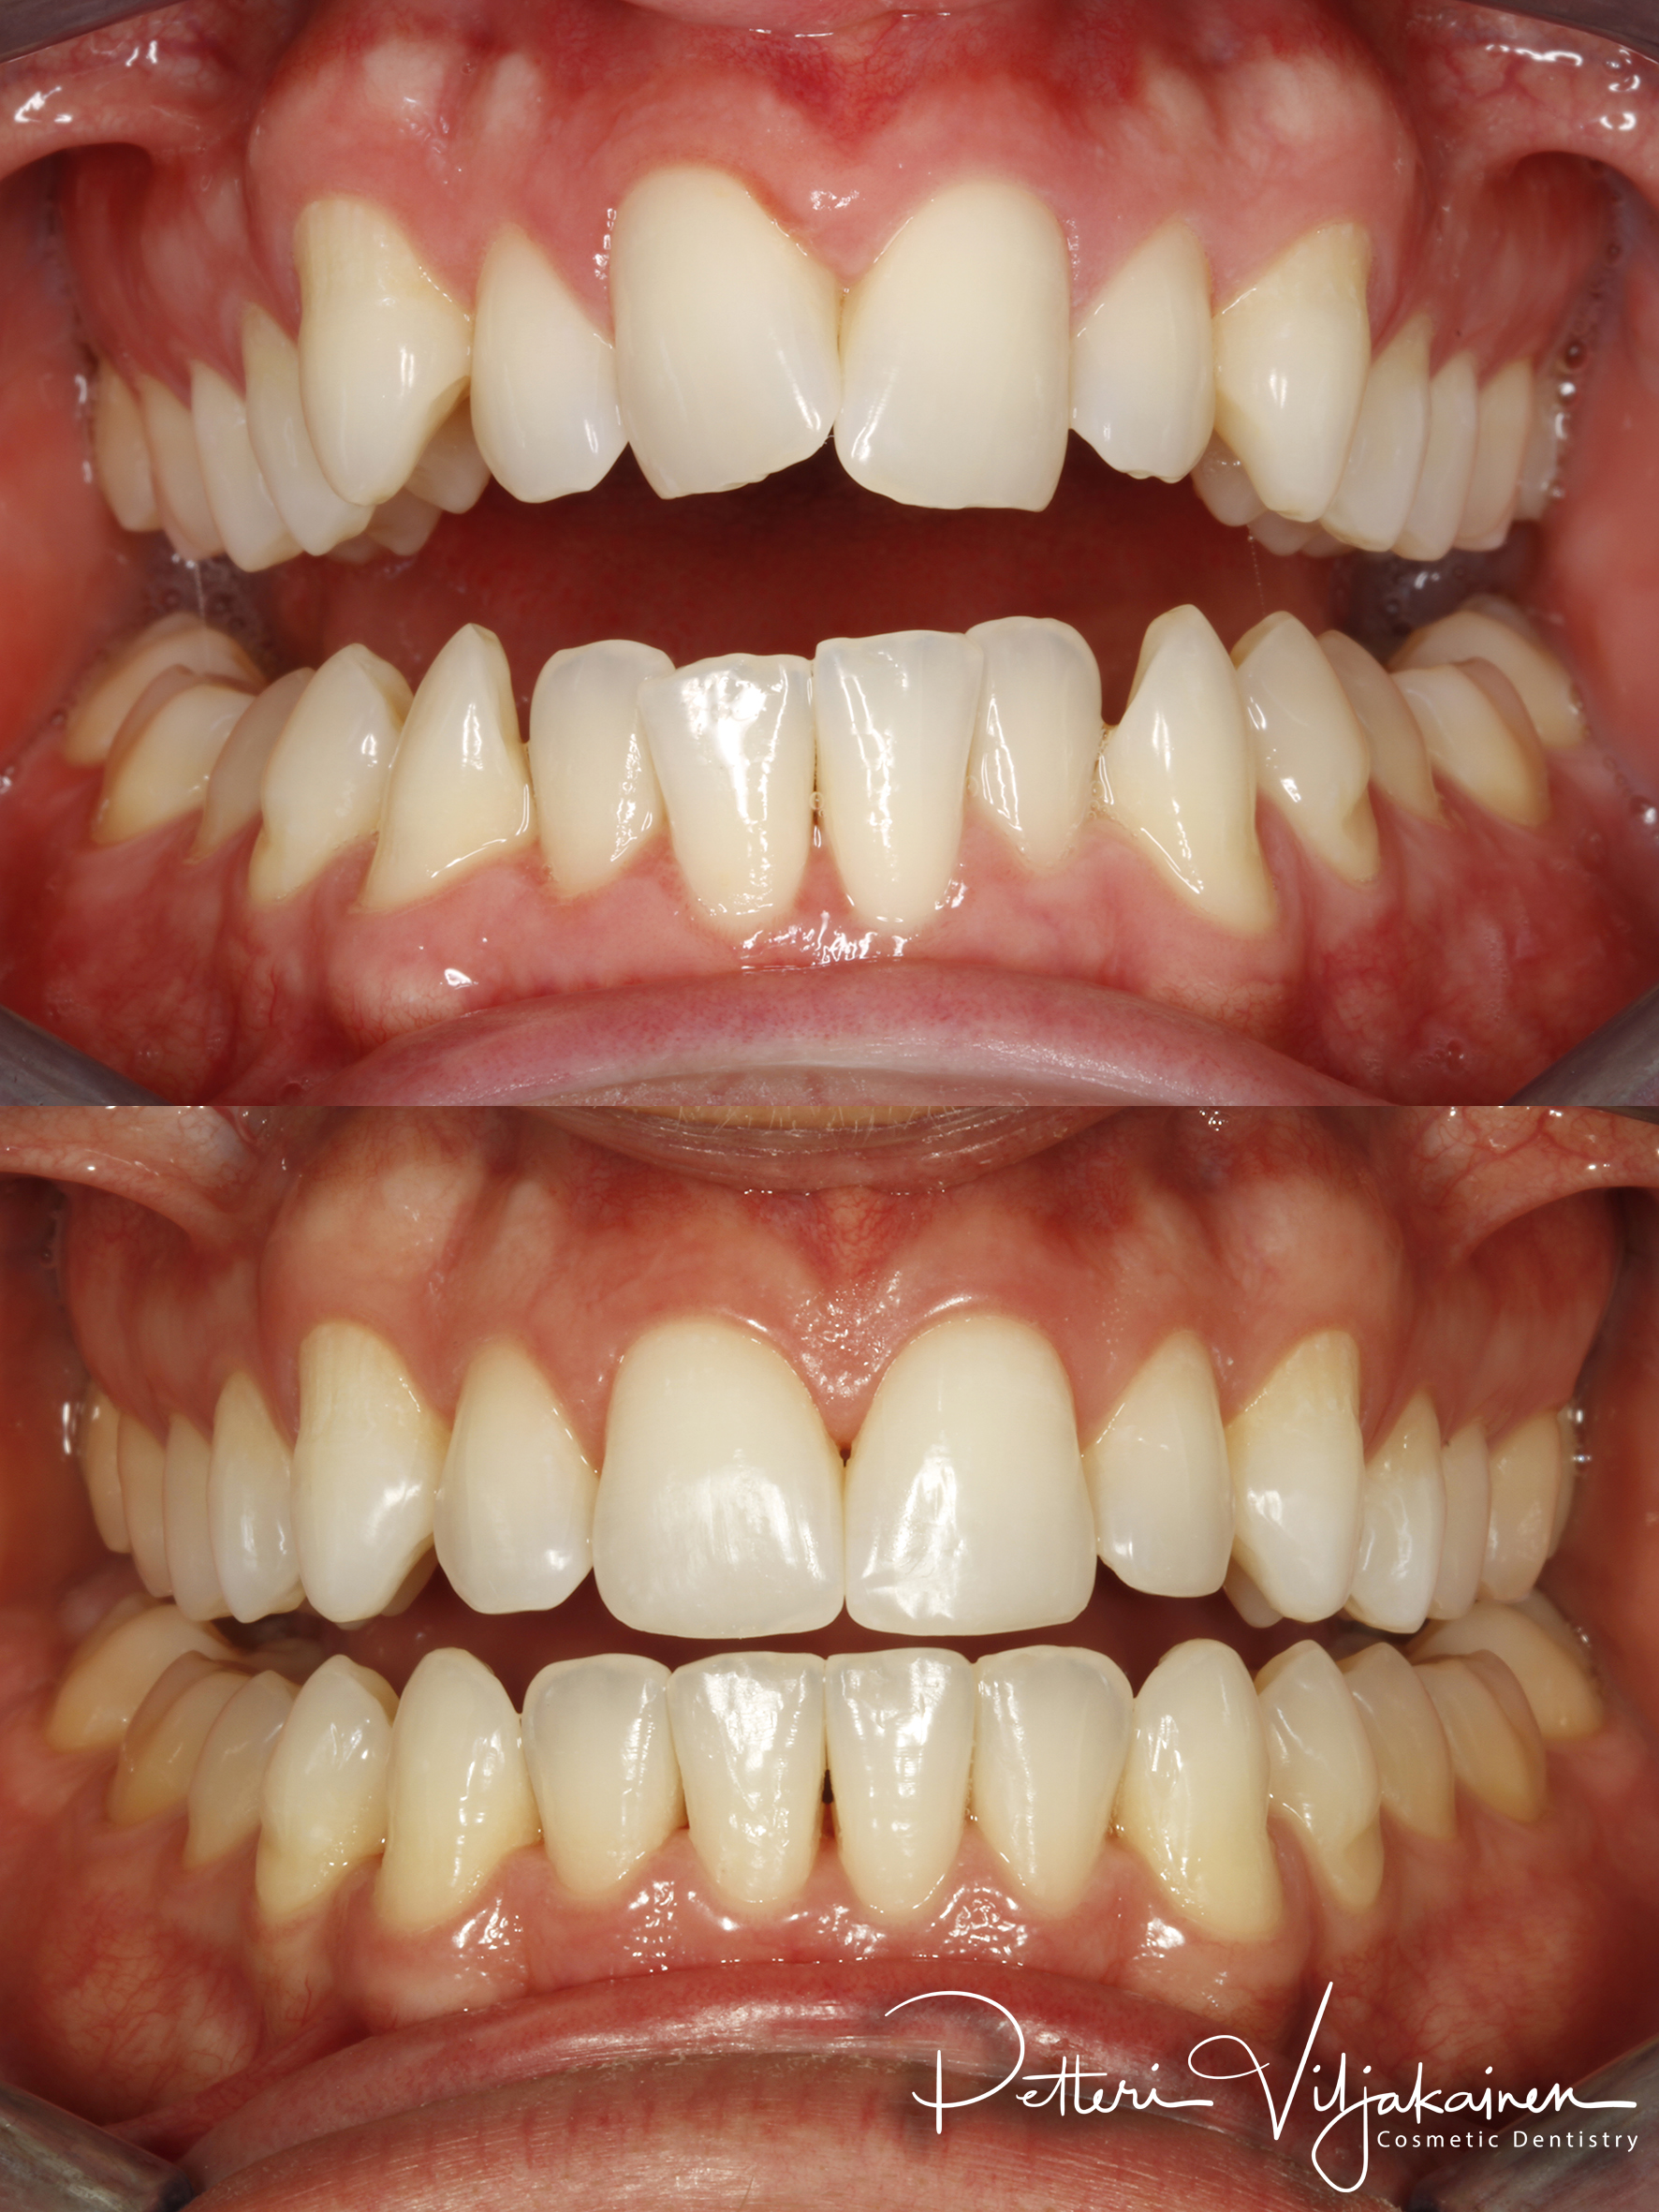

Alla suorittamiani hoitoja ja esimerkkejä siitä minkälaisia purentavirheitä voi korjata.

12kk hoito(Comprehensive).